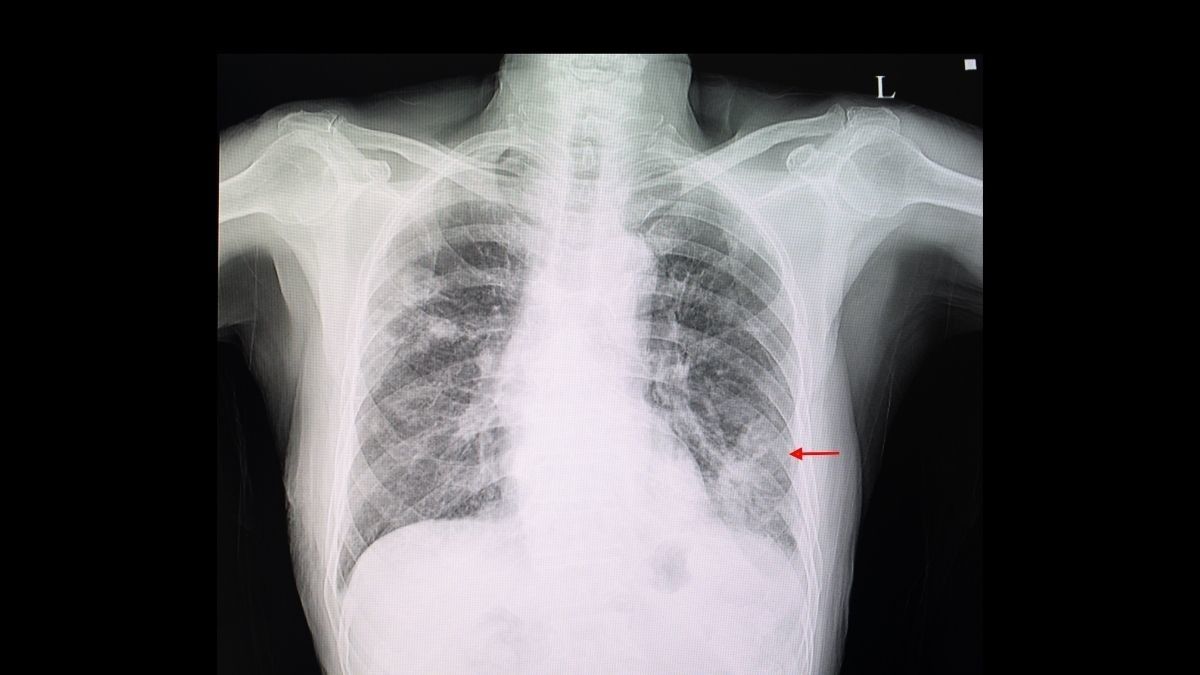

Atelektasis terjadi ketika sebagian atau seluruh bagian paru-paru tidak dapat mengembang dan berfungsi dengan baik. Ada dua jenis atelektasis, yaitu atelektasis obstruktif dan non-obstruktif.

Dijelaskan oleh dr. Atika, secara umum, atelektasis adalah kondisi mengempisnya ruang-ruang alveolus di dalam paru.

Alveolus merupakan tempat pertukaran oksigen dan karbon dioksida. Atelektasis obstruktif terjadi ketika ada sesuatu yang menghalangi saluran napas.

“Penyebab atelektasis obstruktif adalah tersumbatnya bronkus oleh berbagai penyebab. Misalnya karena sputum (dahak), benda asing, tumor, kelenjar getah bening, dan aneurisma (pembesaran pembuluh darah),” ucap dr. Atika.

Sementara itu, atelektasis nonobstruktif dibagi menjadi beberapa bagian berdasarkan penyebabnya, di antaranya:

Lapisan dinding dada dan permukaan paru-paru umumnya saling menempel. Keduanya saling menempel untuk menjaga paru-paru tetap mengembang sempurna.

Namun, adanya cairan atau udara di antara keduanya dapat memisahkan lapisan dinding dada dan permukaan paru-paru.

Celah tersebut menyebabkan paru-paru masuk atau menarik ke dalam sehingga alveolus kehilangan udara.